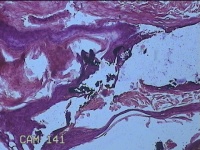

性别

男

年龄

33岁

临床诊断

寻常疣

一般病史

面部起丘疹2年余。

标本名称

面部丘疹

大体所见

灰白暗红色不规则组织0.7x0.5x0.3cm一堆。